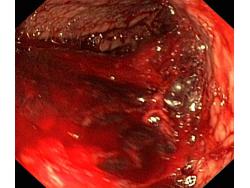

Krwawienie

Wrzód trawienny